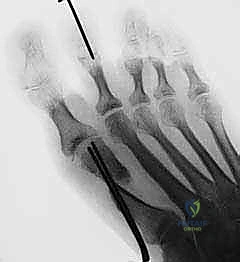

تجهيز القدم للعملية الجراحية. يتم رسم خطوط الشق الجراحي بعناية فائقة لتقليل الندبات وضمان الوصول الأمثل للمفصل.

هذه هي اللحظة الحاسمة في العملية. يقوم الدكتور هطيف بإجراء القص العظمي على شكل حرف (V) ممتد. دقة زاوية القص هنا تحدد نجاح العملية بالكامل.

تُظهر الصورة كيف يتم دفع رأس العظم المشطي إلى مكانه التشريحي الصحيح، مما يقضي على الزاوية المرضية ويعيد للقدم استقامتها.